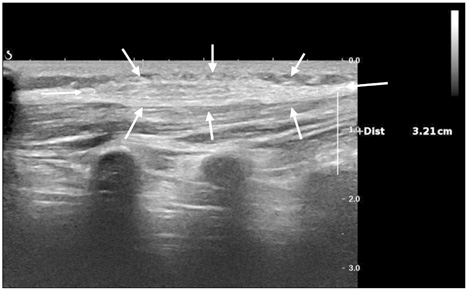

Fig. 3

Microscopic finding of specimen; dense collagenous tissue with balnd spindle cells and adipose tissue (H&E, ×40).

Fig. 3 Microscopic finding of specimen; dense collagenous tissue with balnd spindle cells and adipose tissue (H&E, ×40).